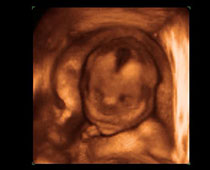

- Fetal Face Ultrasound Photos

- 3D Fetal Profile Ultrasound Scan Photos

- The Clinical Advantages of 3D and 4D Ultrasound

- Definition and Features of Four Dimensional Ultrasound

- Uses of 4D Ultrasound scan